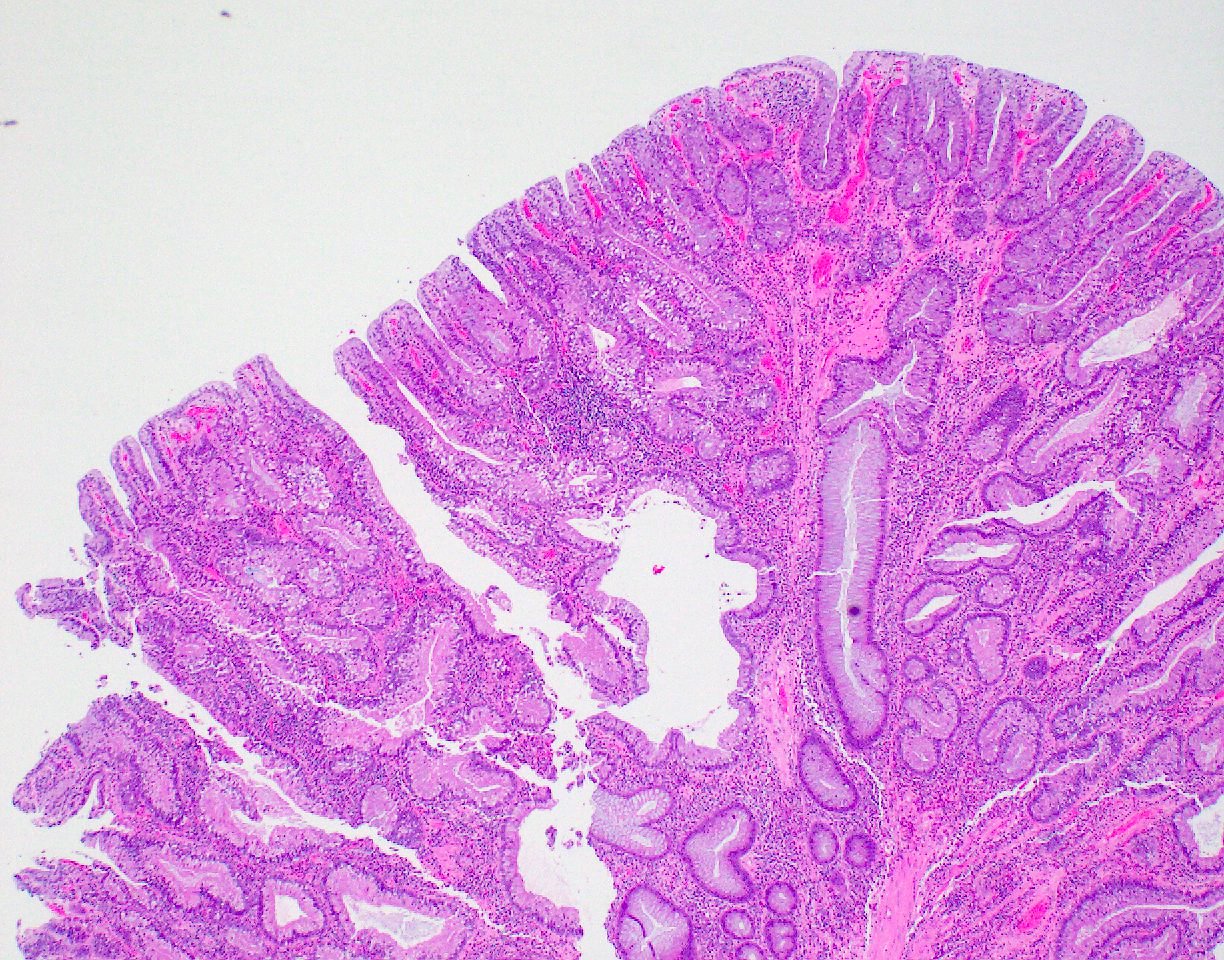

Microscopic (histologic) description

- Polypoid colonic mucosa covered with dysplastic epithelium comprised of hyperchromatic, elongated nuclei arranged in a pseudostratified manner

- Dysplasia is typically low grade but may also be high grade, with architectural (cribriforming, luminal necrosis) and cytologic changes (vesicular chromatin, nucleoli, loss of basal polarity)

- Abrupt transition from normal to dysplastic mucosa is commonly present

- Variable amounts of mucin loss

- Metaplasia may be present: osseous, squamous or Paneth cells (J Clin Pathol 2005;58:220, J Surg Oncol 1984;26:130)

- Pseudoinvasion can mimic progression to adenocarcinoma but displaced glands are benign and surrounded by lamina propria and often hemosiderin (Mod Pathol 2015;28:S88)

- May rarely show clear cell features (Am J Surg Pathol 2010;34:1344)

Microscopic (histologic) images

Contributed by Andrew L.J. Dunn, M.D. and Christopher Hartley, M.D.

Contributed by @Andrew_Fltv and @liverwei on Twitter